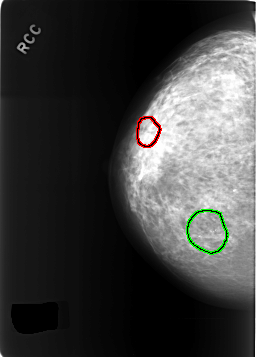

C_0307_1.RIGHT_CC

FILE: C_0307_1.RIGHT_CC.OVERLAY

TOTAL_ABNORMALITIES 2

ABNORMALITY 1

LESION_TYPE CALCIFICATION TYPE PLEOMORPHIC DISTRIBUTION CLUSTERED

LESION_TYPE MASS SHAPE LOBULATED MARGINS CIRCUMSCRIBED

ASSESSMENT 4

SUBTLETY 4

PATHOLOGY BENIGN

TOTAL_OUTLINES 1

ABNORMALITY 2

SUBTLETY 5